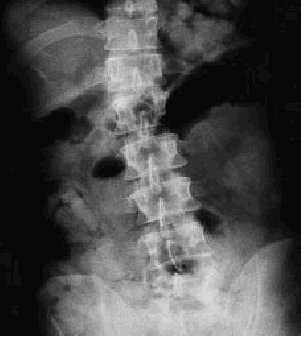

Dada la procedencia del paciente y la sospecha diagnóstica se le realizó una radiografía abdominal (fig. 1), en donde se vieron a nivel del estómago y distribuidas por todo el intestino múltiples imágenes cilíndricas.

Fig. 1.

En la analítica destacaban unos niveles de cocaína de >10.000 ng/ml, diagnosticándose de ingesta de múltiples bolsas de cocaína y sobredosis secundaria a la rotura de una de ellas. Se le administró una solución evacuante, tras la cual el paciente presentó obstrucción intestinal, siendo necesario intervenirle de urgencia.

El paciente llevaba 80 bolsas de cocaína de 10 gramos cada una.